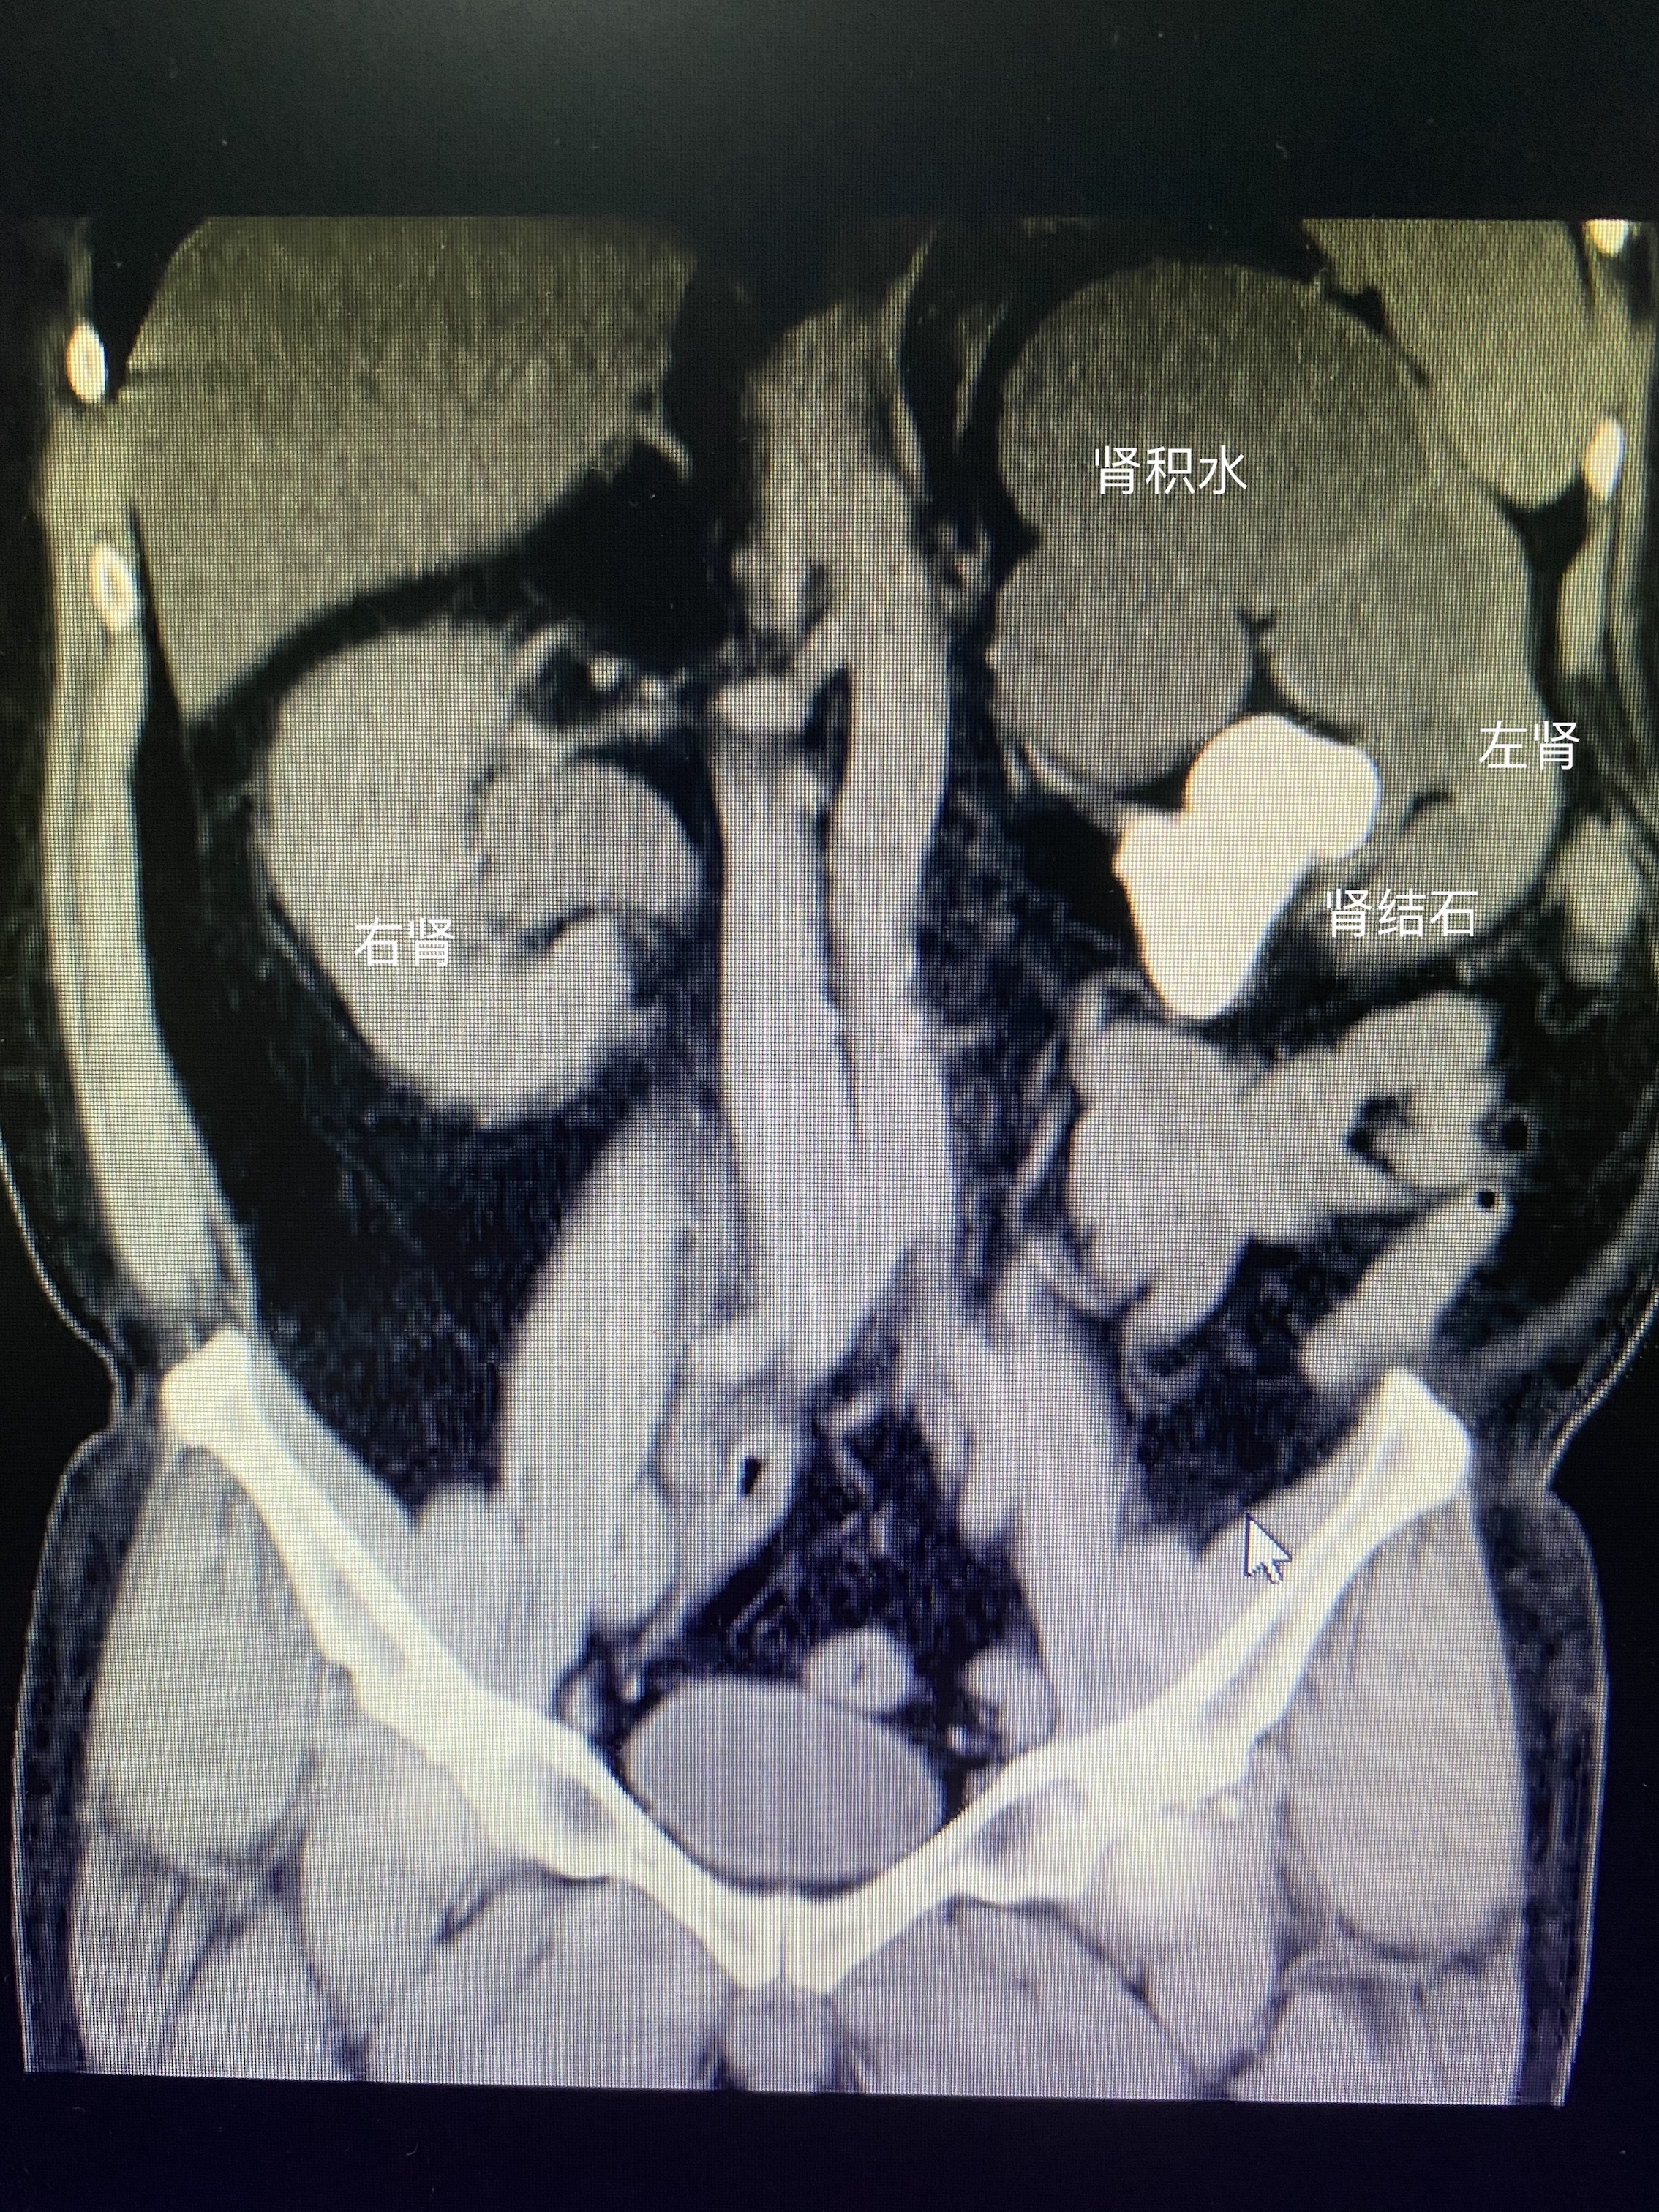

当然不是,如果肾结石的体积较大,白色的肾结石已经导致左边肾脏较重的肾积水,肾积水已经将左边的肾脏组织挤压了。和右边的肾脏相比,左边的肾脏已经压缩的非常小了。那么像这种体积较大的肾结石,也是需要立即处理的。

CT检查